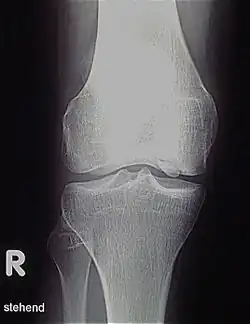

MRT-Bild einer Osteochondrosis dissecans des Kniegelenkes

Die Osteochondrosis dissecans (kurz OCD bzw. OD, angloamerikanisch auch Osteochondritis dissecans) ist eine umschriebene Knochenläsion unterhalb des Gelenkknorpels, die im ungünstigen Fall mit einer Separation und Abstoßung des betroffenen Knochenareals mit dem darüberliegenden Knorpel als freier Gelenkkörper (Gelenkmaus) enden kann. Es verbleibt dann ein Gelenkflächendefekt (Mausbett). Es besteht aber auch die Möglichkeit einer spontanen Ausheilung oder einer Ausheilung unter therapeutischen Maßnahmen. Es handelt sich nicht um eine primäre Knochennekrose, sondern um die Folgen einer Chondronekrose in der sekundären Physe (s. u.) Die OCD kann die meisten großen Gelenke des menschlichen Körpers betreffen, sie tritt aber vor allem im Kniegelenk, im oberen Sprunggelenk und im Ellbogengelenk auf. Aufgrund konzentrierter mechanischer Einwirkung tritt die OD jedoch fast ausschließlich in konvexen Gelenkanteilen wie dem Femurkondylus, der Talusrolle, dem Condylus radialis des Humerus und am Femurkopf auf. Die klassische Osteochondrosis dissecans kommt bei Kindern und Jugendlichen vor, da für die Entstehung noch offene Wachstumsfugen die entscheidende Voraussetzung sind. OCD bei Erwachsenen ist keine separate Erkrankung, sondern eine Form, die im Jugendalter nicht erkannt wurde, weil sie möglicherweise symptomarm verlief. Dieser Artikel orientiert sich vor allem an der Lokalisation Knie. In der Veterinärmedizin kommt sie insbesondere bei großen Hunderassen (Schulter, Ellbogen, Knie, Sprunggelenk etc.) und bei Mastschweinen vor. Inwieweit osteochondrale Ablösungen in Gelenken (Chips) bei Pferden dem gleichen Pathomechanismus unterliegen, bleibt zu klären.

Röntgenbild: Osteochondrose mit Dissekat noch im Verbund des medialen Kondylus

Diagnose

Die Erkrankung kann zufällig auf einem Röntgenbild entdeckt werden, das nach einem Unfall von der Knieregion, vom Sprunggelenk oder vom Ellbogen angefertigt wird. Bei typischen Beschwerden von aktiven Kindern und Jugendlichen kann mit einem solchen einfachen Röntgenbild die eindeutige Diagnose schon gestellt werden, weil der veränderte Knochen unterhalb der Gelenkoberfläche an typischer Stelle in der Oberschenkelrolle am Knie identifiziert werden kann. Manchmal kann eine sogenannte Tunnelaufnahme mit gebeugtem Knie die Schädigungszone noch besser zeigen. Zur genaueren Analyse sollte eine Kernspintomographie (MRT) durchgeführt werden. An den dabei erzeugten Bildern lässt sich die Lage und Größe des Befundes, die Tiefenausdehnung und vor allem eine Beteiligung des darüberliegenden Knorpels genau ausmessen. Es sind damit auch Aussagen zur Stabilität des Befundes zu treffen. Daraus ergeben sich dann entscheidende Anhaltspunkte für therapeutische Konsequenzen. Für die Verlaufsbeurteilung der Erkrankung eignet sich am besten das MRT, aber ggf. auch wieder die einfache Röntgenuntersuchung. Aufgrund der extrem hohen Kosten für das MR in den USA werden die Verläufe dort bis heute weitgehend nur mit Röntgenbildern dokumentiert, was zu eigenen Empfehlungen zur Verlaufsbeurteilungen führt. Generell wären aber die MR-Untersuchungen das Verfahren der Wahl. Sie erlauben eine differenzierte Beurteilung der unterschiedlichen Kriterien für Ausheilung, Instabilität und drohende Dissektion. Untersuchungen mit Sonographie können zuverlässige, aber nur orientierende Befunde am Femurkondylus erheben. Es ist damit zum Beispiel ein schneller, kostengünstiger und sicherer Ausschluss des Befalls auch der Gegenseite möglich.